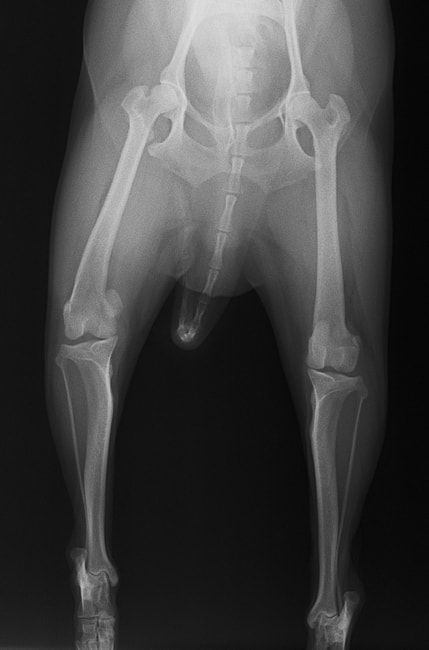

■ 症例22 ポメラニアン 1歳5か月 去勢雄

左後肢の挙上を主訴に来院した。整形学的検査、レントゲン検査より左右の膝蓋骨脱臼(左GradeⅡ〜Ⅲ、右Grade Ⅱ)を認めた。また、脛骨の前方引き出し試験の際に、引き出し兆候は認められないものの、疼痛が認められたため、前十字靭帯の損傷が疑われた。術中における、目視および関節内の操作によって、前十字靭帯の損傷や過伸展といった異常が認められなかったため、膝蓋骨脱臼の整復のみ実施した。手術手技は縫工筋及び内側広筋の解放、脛骨粗面の外側転位、滑車ブロック形造溝術、内外側関節包の縫縮を実施した。本症例は跛行もなく経過良好である。しかし、頸骨高平部の角度(TPA)が 右26.2°、左24.9°であり、解剖学的に前十字靭帯損傷のリスクが高いことから今後の経過に注意が必要である。